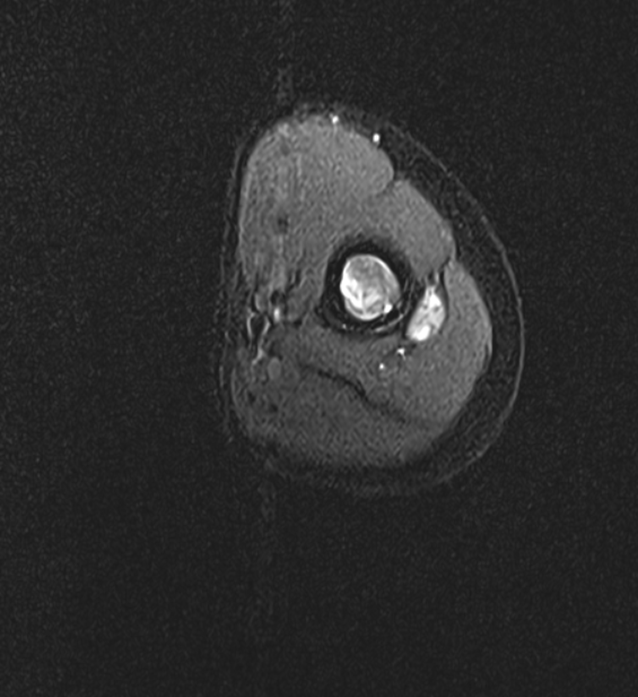

View CaseA 39 year old female presented with lower back pain and leg pain since 3 months.

A 39 year old female presented with lower back pain and leg pain since 3 months.